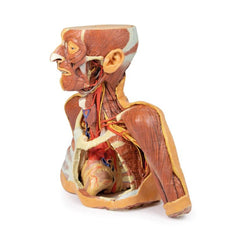

3D Printed Head and Visceral Column of the Neck

The face: On the right side of the head the parotid gland has been removed to reveal the facial nerve and all its branches (temporal, zygomatic, buccal, marginal mandibular and cervical) and demonstrate the spatial relations of structures embedded in the gland from superficial to deep (facial nerve, retromandibular vein, external carotid artery). In the surrounding region the temporalis, masseter and posterior belly of digastric are exposed, as are and the facial artery, transverse facial artery and superficial temporal artery. The facial vein and transverse facial vein are clearly visible uniting to form the common facial vein which is joined by the retromandibular vein to form the external jugular vein.

Viewed from the anterior aspect the face has been dissected to display some of the facial muscles around the mouth (buccinator [on the left], orbicularis oris and zygomaticus major). On the left side of the infratemporal fossa has been open to expose the medial and lateral pterygoids.

The lateral pterygoid is divided to show the mandibular division of the trigeminal nerve dividing into the lingual nerve and the inferior alveolar branch. Also on the left side the branches of the ophthalmic division of the trigeminal that supply the skin above the eyebrows and scalp (supraorbital [left only] and supratrochlear nerves [both sides]) are dissected. The submandibular gland is clearly visible below the mandible on both sides as are the facial arteries and veins as they course over the mandible.

The neck: The musculoskeletal portion of the neck have been removed to display the pharynx posteriorly, the larynx anteriorly, and the neurovascular bundles laterally. The suprahyoid and infrahyoid muscles can be seen on the neck, as well as the cricothyroid muscle.

When looking up the length of the trachea from below, the vocal folds are visible. The hypoglossal nerve can be seen winding around the lateral surface of the external carotid artery and the external branch of superior laryngeal nerve is seen descending in the neck. The internal jugular vein, the common carotid artery and its bifurcation into external and internal carotid arteries are clearly seen on both left and right. The vagus nerve in the carotid sheath is also visible. The ansa cervicalis is visible emerging below the digastric muscle and descending on the surface of the internal jugular vein. The internal branch of the superior laryngeal nerve can be seen below the superior thyroid artery on the left. The superior thyroid artery branching from the external carotid artery is seen descending in the anterior neck. The internal branch of the superior laryngeal artery is visible on the left piercing the thyrohyoid membrane above the inferior constrictor where this muscle is attached to the hyoid bone.

Posterior view of the pharynx: The superior, middle and inferior pharyngeal constrictors are indicated on the pharynx wall. The oesophagus can be identified emerging from the lower end of the pharynx. The posterior horn of the hyoid bone acts as a useful landmark. The carotid sheath seen from behind clearly shows the vagus nerve and its pharyngeal branches on the left. The recurrent laryngeal nerve is briefly visible on the left lying medial to the inferior thyroid artery. The occipital arteries are visible as they curve around the mastoid process. The vertebral arteries are seen either side of the brainstem as they enter the foramen magnum. The cerebellum has been removed to allow the fourth ventricle to be exposed. The cut surfaces of the cerebellar peduncles are clearly visible. A large portion of the posterior inferior cerebellar artery on the right is still visible as it winds around around the brainstem.

Cranial Cavity: The left and right orbits have been opened to reveal the orbital nerves and vessels along with the eyes and optic nerves. The optic chiasm, optic tracts and the lateral geniculate bodies are retained thus showing a large part of the visual pathways. The brainstem is cut at the level of the superior colliculi on the left and slightly lower on the right. The olfactory tracts and bulbs are also demonstrated. The origins of many of the cranial nerves from the brainstem are clearly visible.

3D Printed Head and Visceral Column of the Neck

This 3D print specimen preserves a series of features of the head and visceral column of the neck:The face: On the right side of the head the parotid gland has been removed to reveal the facial nerve and all its branches (temporal, zygomatic, buccal, marginal mandibular and cervical) and demonstrate the spatial relations of structures embedded in the gland from superficial to deep (facial nerve, retromandibular vein, external carotid artery). In the surrounding region the temporalis, masseter and posterior belly of digastric are exposed, as are and the facial artery, transverse facial artery and superficial temporal artery. The facial vein and transverse facial vein are clearly visible uniting to form the common facial vein which is joined by the retromandibular vein to form the external jugular vein.

Viewed from the anterior aspect the face has been dissected to display some of the facial muscles around the mouth (buccinator [on the left], orbicularis oris and zygomaticus major). On the left side of the infratemporal fossa has been open to expose the medial and lateral pterygoids.

The lateral pterygoid is divided to show the mandibular division of the trigeminal nerve dividing into the lingual nerve and the inferior alveolar branch. Also on the left side the branches of the ophthalmic division of the trigeminal that supply the skin above the eyebrows and scalp (supraorbital [left only] and supratrochlear nerves [both sides]) are dissected. The submandibular gland is clearly visible below the mandible on both sides as are the facial arteries and veins as they course over the mandible.

The neck: The musculoskeletal portion of the neck have been removed to display the pharynx posteriorly, the larynx anteriorly, and the neurovascular bundles laterally. The suprahyoid and infrahyoid muscles can be seen on the neck, as well as the cricothyroid muscle.

When looking up the length of the trachea from below, the vocal folds are visible. The hypoglossal nerve can be seen winding around the lateral surface of the external carotid artery and the external branch of superior laryngeal nerve is seen descending in the neck. The internal jugular vein, the common carotid artery and its bifurcation into external and internal carotid arteries are clearly seen on both left and right. The vagus nerve in the carotid sheath is also visible. The ansa cervicalis is visible emerging below the digastric muscle and descending on the surface of the internal jugular vein. The internal branch of the superior laryngeal nerve can be seen below the superior thyroid artery on the left. The superior thyroid artery branching from the external carotid artery is seen descending in the anterior neck. The internal branch of the superior laryngeal artery is visible on the left piercing the thyrohyoid membrane above the inferior constrictor where this muscle is attached to the hyoid bone.

Posterior view of the pharynx: The superior, middle and inferior pharyngeal constrictors are indicated on the pharynx wall. The oesophagus can be identified emerging from the lower end of the pharynx. The posterior horn of the hyoid bone acts as a useful landmark. The carotid sheath seen from behind clearly shows the vagus nerve and its pharyngeal branches on the left. The recurrent laryngeal nerve is briefly visible on the left lying medial to the inferior thyroid artery. The occipital arteries are visible as they curve around the mastoid process. The vertebral arteries are seen either side of the brainstem as they enter the foramen magnum. The cerebellum has been removed to allow the fourth ventricle to be exposed. The cut surfaces of the cerebellar peduncles are clearly visible. A large portion of the posterior inferior cerebellar artery on the right is still visible as it winds around around the brainstem.

Cranial Cavity: The left and right orbits have been opened to reveal the orbital nerves and vessels along with the eyes and optic nerves. The optic chiasm, optic tracts and the lateral geniculate bodies are retained thus showing a large part of the visual pathways. The brainstem is cut at the level of the superior colliculi on the left and slightly lower on the right. The olfactory tracts and bulbs are also demonstrated. The origins of many of the cranial nerves from the brainstem are clearly visible.